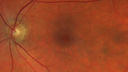

51 year old female on with trouble driving at night for a year. No eye examination for several years. 2009 (11 years ago) Plaquenil 300 then up to 400 a few years ago now down to 300 - 5'2" 135 lbs

VA 20/20 OD, 20/25 OS